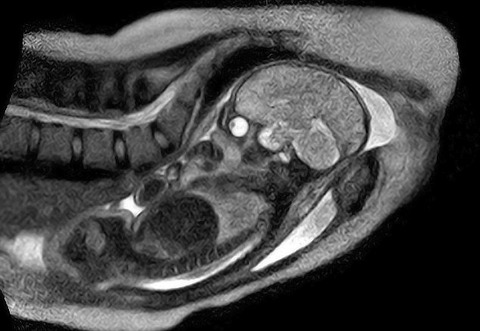

世界初! 出産時の胎児の様子をMRIで撮影。

ベルリンの病院で、世界で初めて出産の様子がMRI撮影されました。上の画像がそれです。 今まさに母親の中の世界から外に出ようとしている赤ちゃんがとても鮮明に美しく写っていますね。ベルリンの Charite病院で、特別な「オープンタイプ」のMRIスキャナー(通常はチューブのような形状をしている)を用いり、出産のためのスペースを充分に確保、出産の時の赤ちゃんの様子をMRIで撮影したそうです。

これは出産における胎児の細かい動きなど、あくまでも科学的な事由においてのみ使うと約束された上での撮影でした。このリアルなMRI画像は、合併症や出産時のプロセスの落とし穴を理解する上で、重要な証拠となるのだそうです。